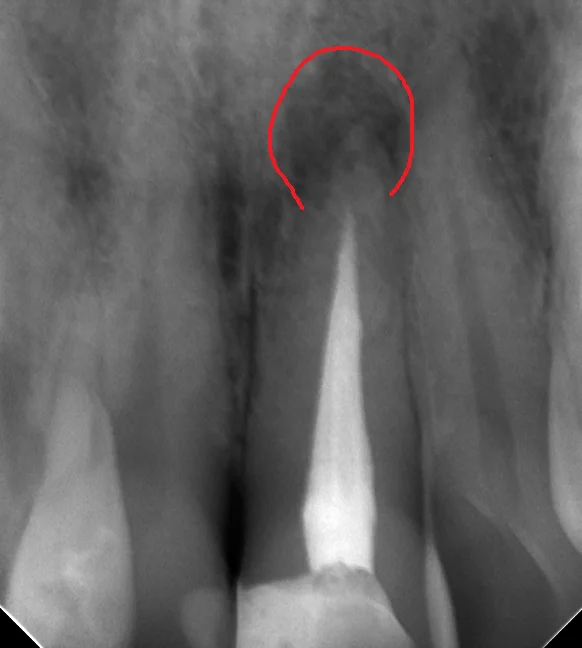

神経の治療がダメになるとどうなるかというと、画像の赤で囲まれている所のように根の先に膿が溜まってきます。

根の先に膿が溜まった状態で長期間放置することで、根管(神経の管)内に限局していた感染源が根管の外に出てしまい、そこで巣を作ることがあります。

そうなると神経の治療でどれだけ根管内を綺麗にしても、原因は根管の外に出ているので治りません。

なので、レントゲン上で膿が認められて、担当医から「治療した方が良い」と言われた場合は早めに治療に入った方が無難です。